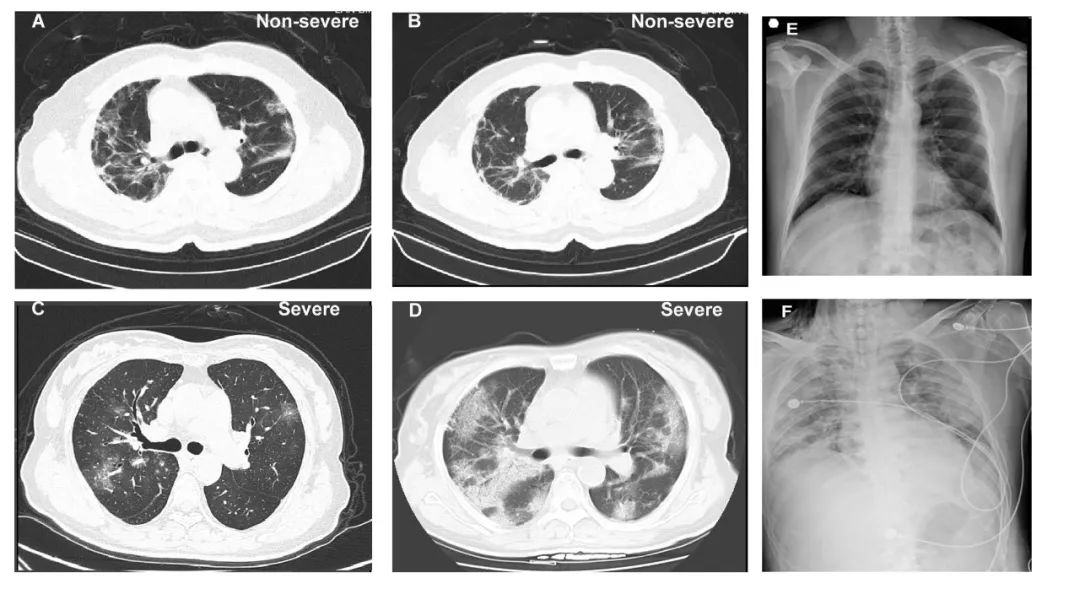

钟南山领衔发布近1100例新冠肺炎患者临床数据!